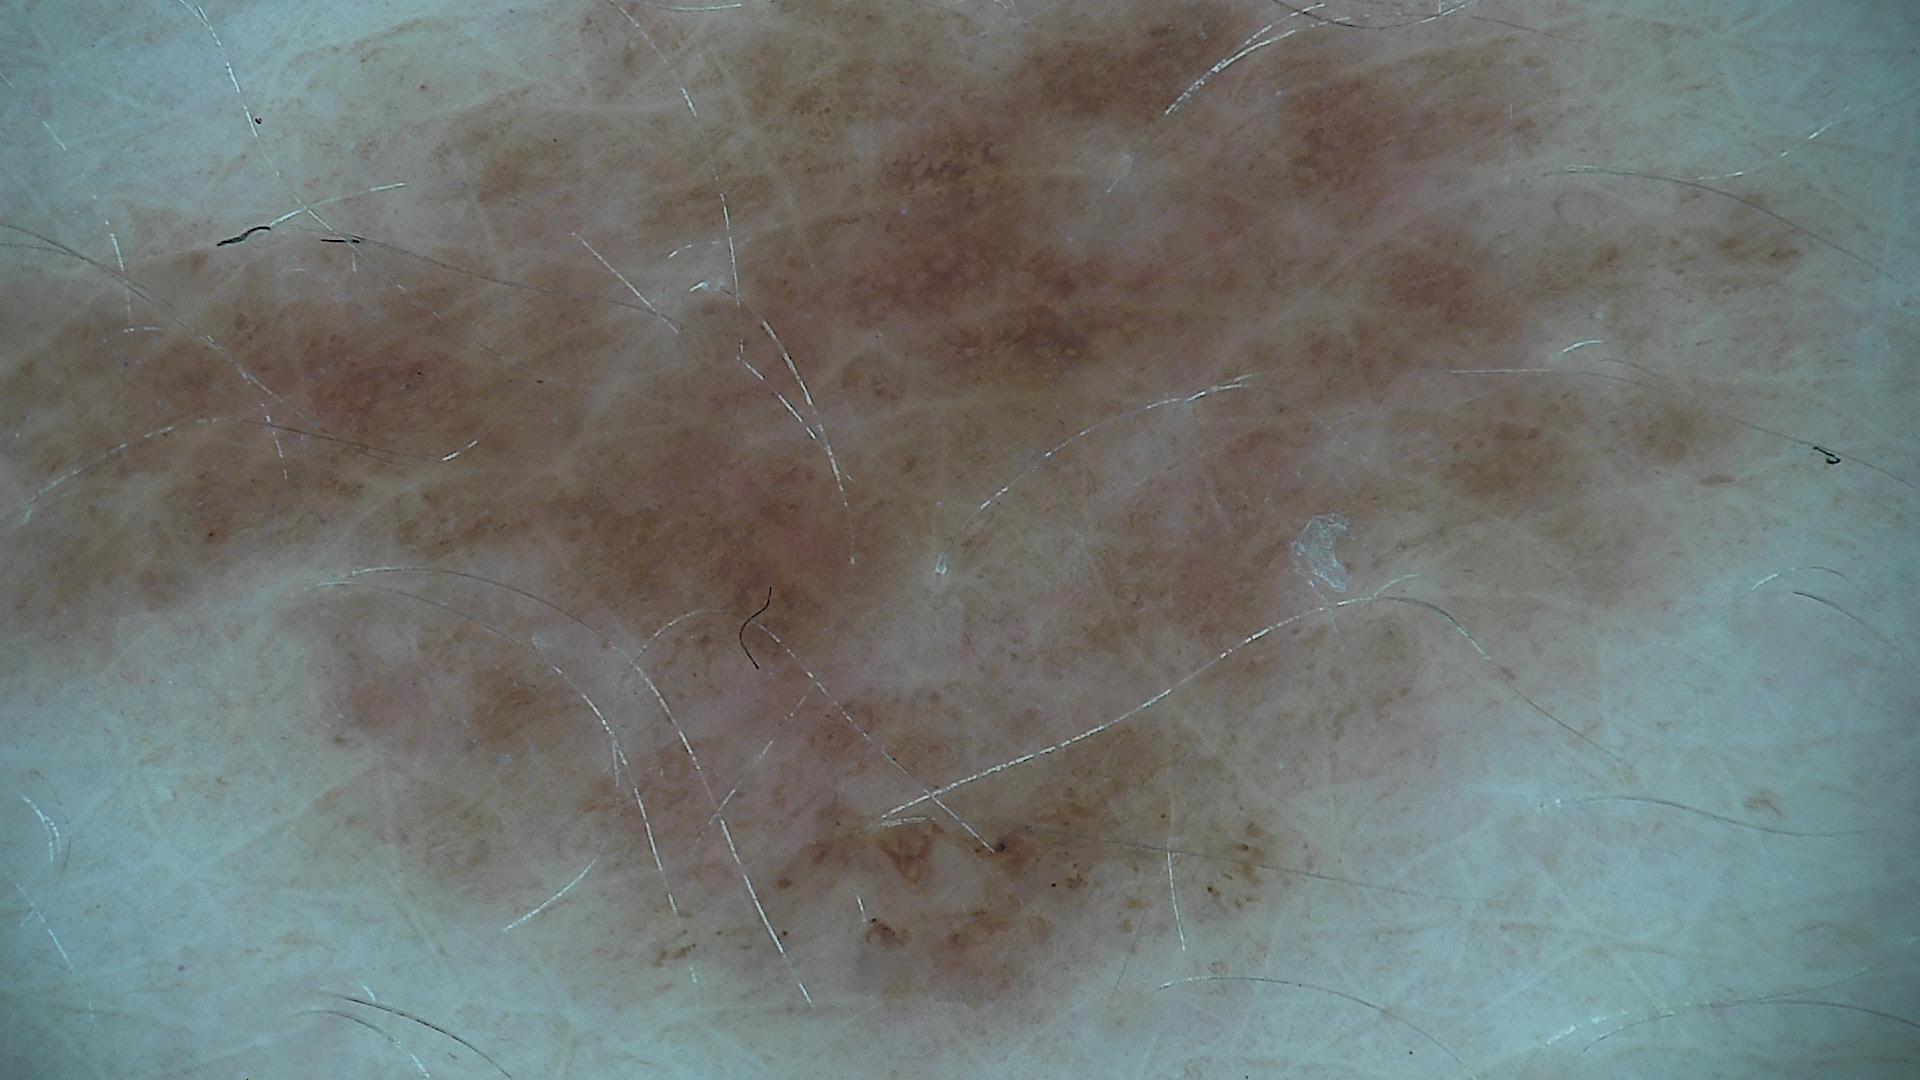

ISIC_5605974

1920 x 1080

Imperial College London

diagnosis_1

Benign

diagnosis_2

Benign melanocytic proliferations

diagnosis_3

Nevus

diagnosis_4

Nevus, NOS, Compound

image_type

dermoscopic

melanocytic

True